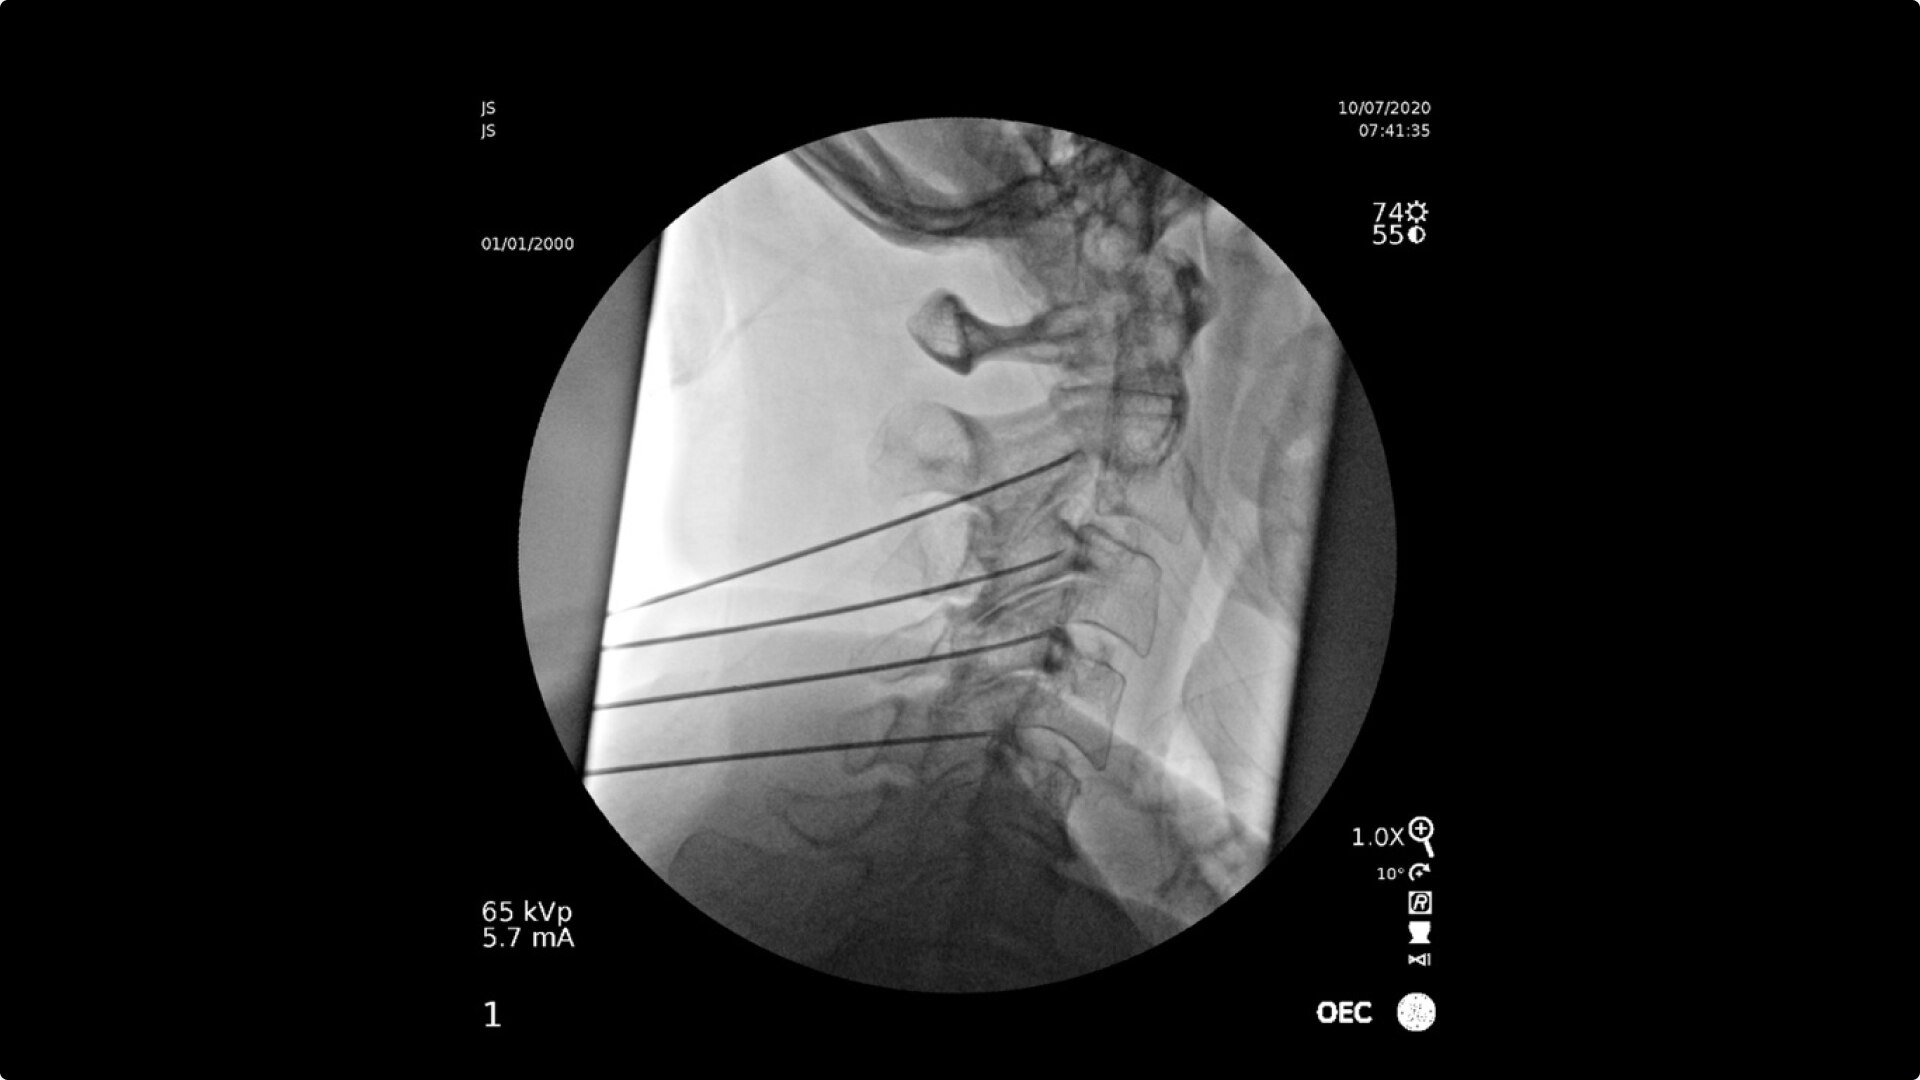

C-arms for Pain Management

Consistently experience amazing image quality, precision, and efficiency during simple to complex pain management procedures with OEC C-arms.

With choice of C-arms to fit a variety of needs, easily obtain challenging spine angles with a 55° overscan, rainbows without moving the base, or a motorized drive.

Pain Management procedures require powerful imaging systems.

OEC C-arms perform imaging in a variety of procedures such as:

• Steroid injections

• Radiofrequency treatments

• Contrast media injections

• Cervical spine pain management

• Thoracolumbar procedures